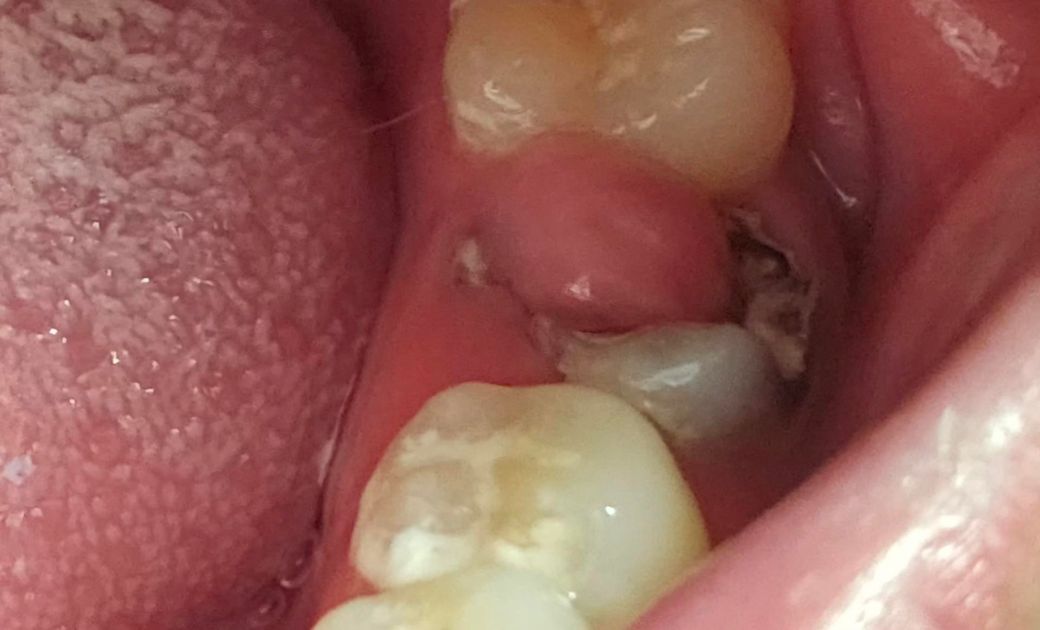

이빨이정도상태인데요?

치과에서 신경치료 아니면 뽑아하는상태인가요?

현상태는 치아가 충치로 깨져나갔고 그로 인해 신경이 노출된 상태입니다 그러다보니 치수가 자극을 받아 저렇게 용종이 생겼고요 신경치료 시도는 해볼 수 있으나 발치 가능성 높습니다